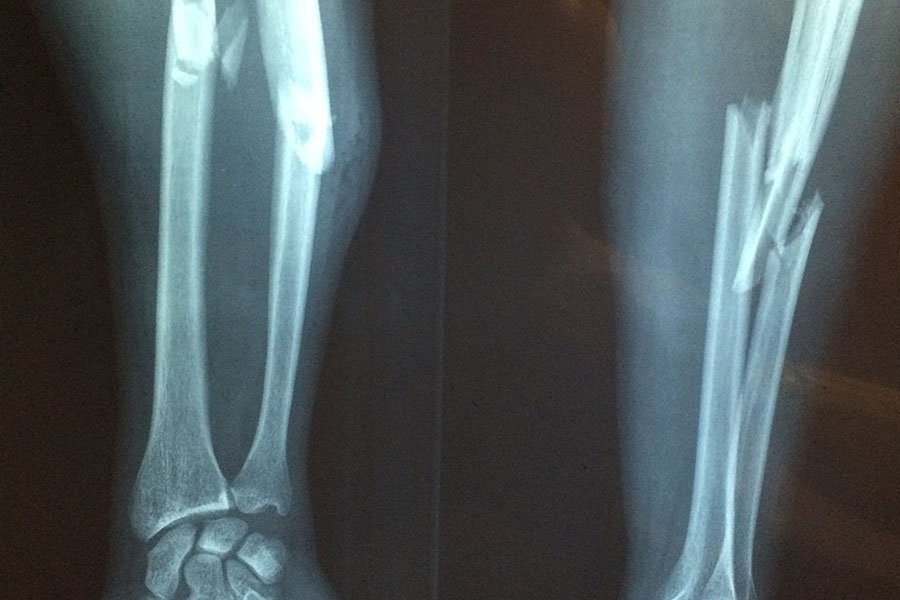

Переломы вследствие хрупкости костей, часто вызываемые остеопорозом (заболеванием, вызывающим хрупкость костей, склонных к переломам), поражают каждую вторую женщину и каждого четвертого мужчину, причем основным фактором риска является низкая минеральная плотность костной ткани (МПК).